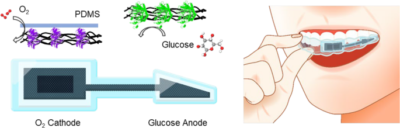

東北大学 西澤松彦先生 口腔用デバイスの論文figure制作

Matsuura, M., Suzuki, S., Cho, H., Osaki, S., Tottori, S., & Nishizawa, M. (2026). Fully organic waterproof biobattery designed for mouthpiece applications. Biomedical Microdevices, 28(2), 38.

東北大学 西澤松彦先生 口腔用デバイスの論文figure制作

東北大学 工学研究科・医工学研究科 2026.05